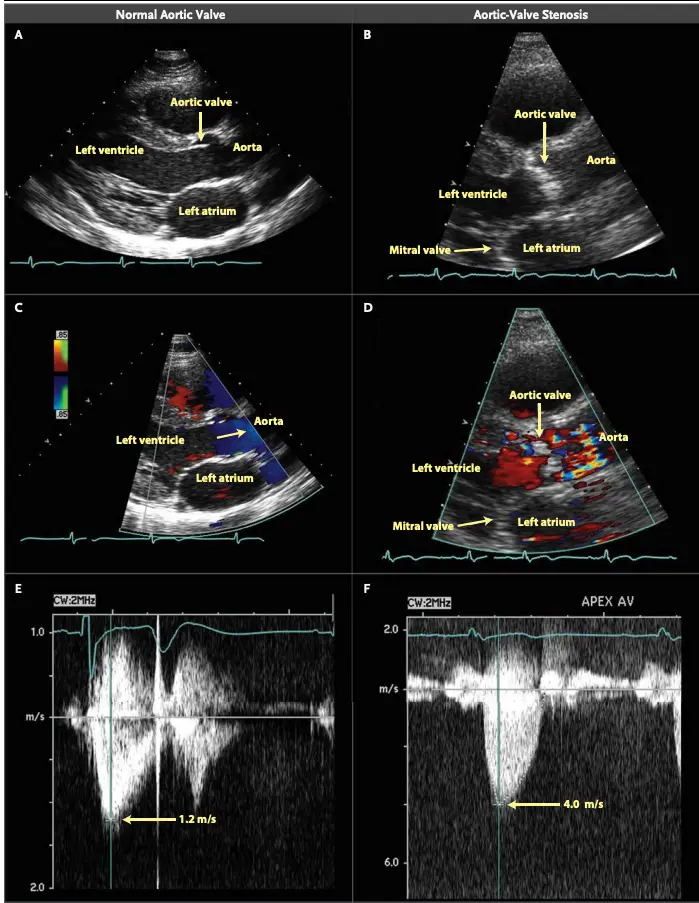

Echo for Valvular AS

Board Pearl: If normal Aortic Valve on 2D-echo and high gradient, think subvalvular AS, e.g. Subaortic Stenosis, or supravalvular AS.

- Cannot tell severity of stenosis with 2D-echo alone. You will need Doppler to help determine severity of AS.

- ==Valvular AS will be considered severe if mean gradient > 40 mmHg or peak velocity > 4 m/s (regardless of AVA)==

- Aortic velocity is measured using continuous-wave doppler ultrasound with examination from multiple acoustic windows

Underestimation due to improper Doppler alignment across the Aortic Valve

If not parallel to the AS jet, you will not get the highest mean AV gradient or peak velocity across the AV → underestimate severity of AS. Importantly, you cannot overestimate the gradient (Exceptions: significant anemia or Subaortic Stenosis).

- The above figure is from the Mayo Echo Boards video where the presenter highlights the importance of calculating the AV TVI in multiple windows to ensure you are appropriately calculating the highest VTI and avoid miscalculation/miscalssification. In Thaden et al (JASE, 2015), the authors found that peak velocity was found outside of the apical window 61% of the time and that neglecting non-apical window misclassified AS 23% of the time.